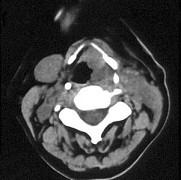

问题 女、54岁,鼻咽部异物感约三个月,PE:左侧声带固定,可见肿物,CT如图所示,应诊断为()

选项 A.喉部乳头状瘤 B.喉癌 C.喉部血管瘤 D.慢性增生性喉炎 E.增生型喉结核

答案 B